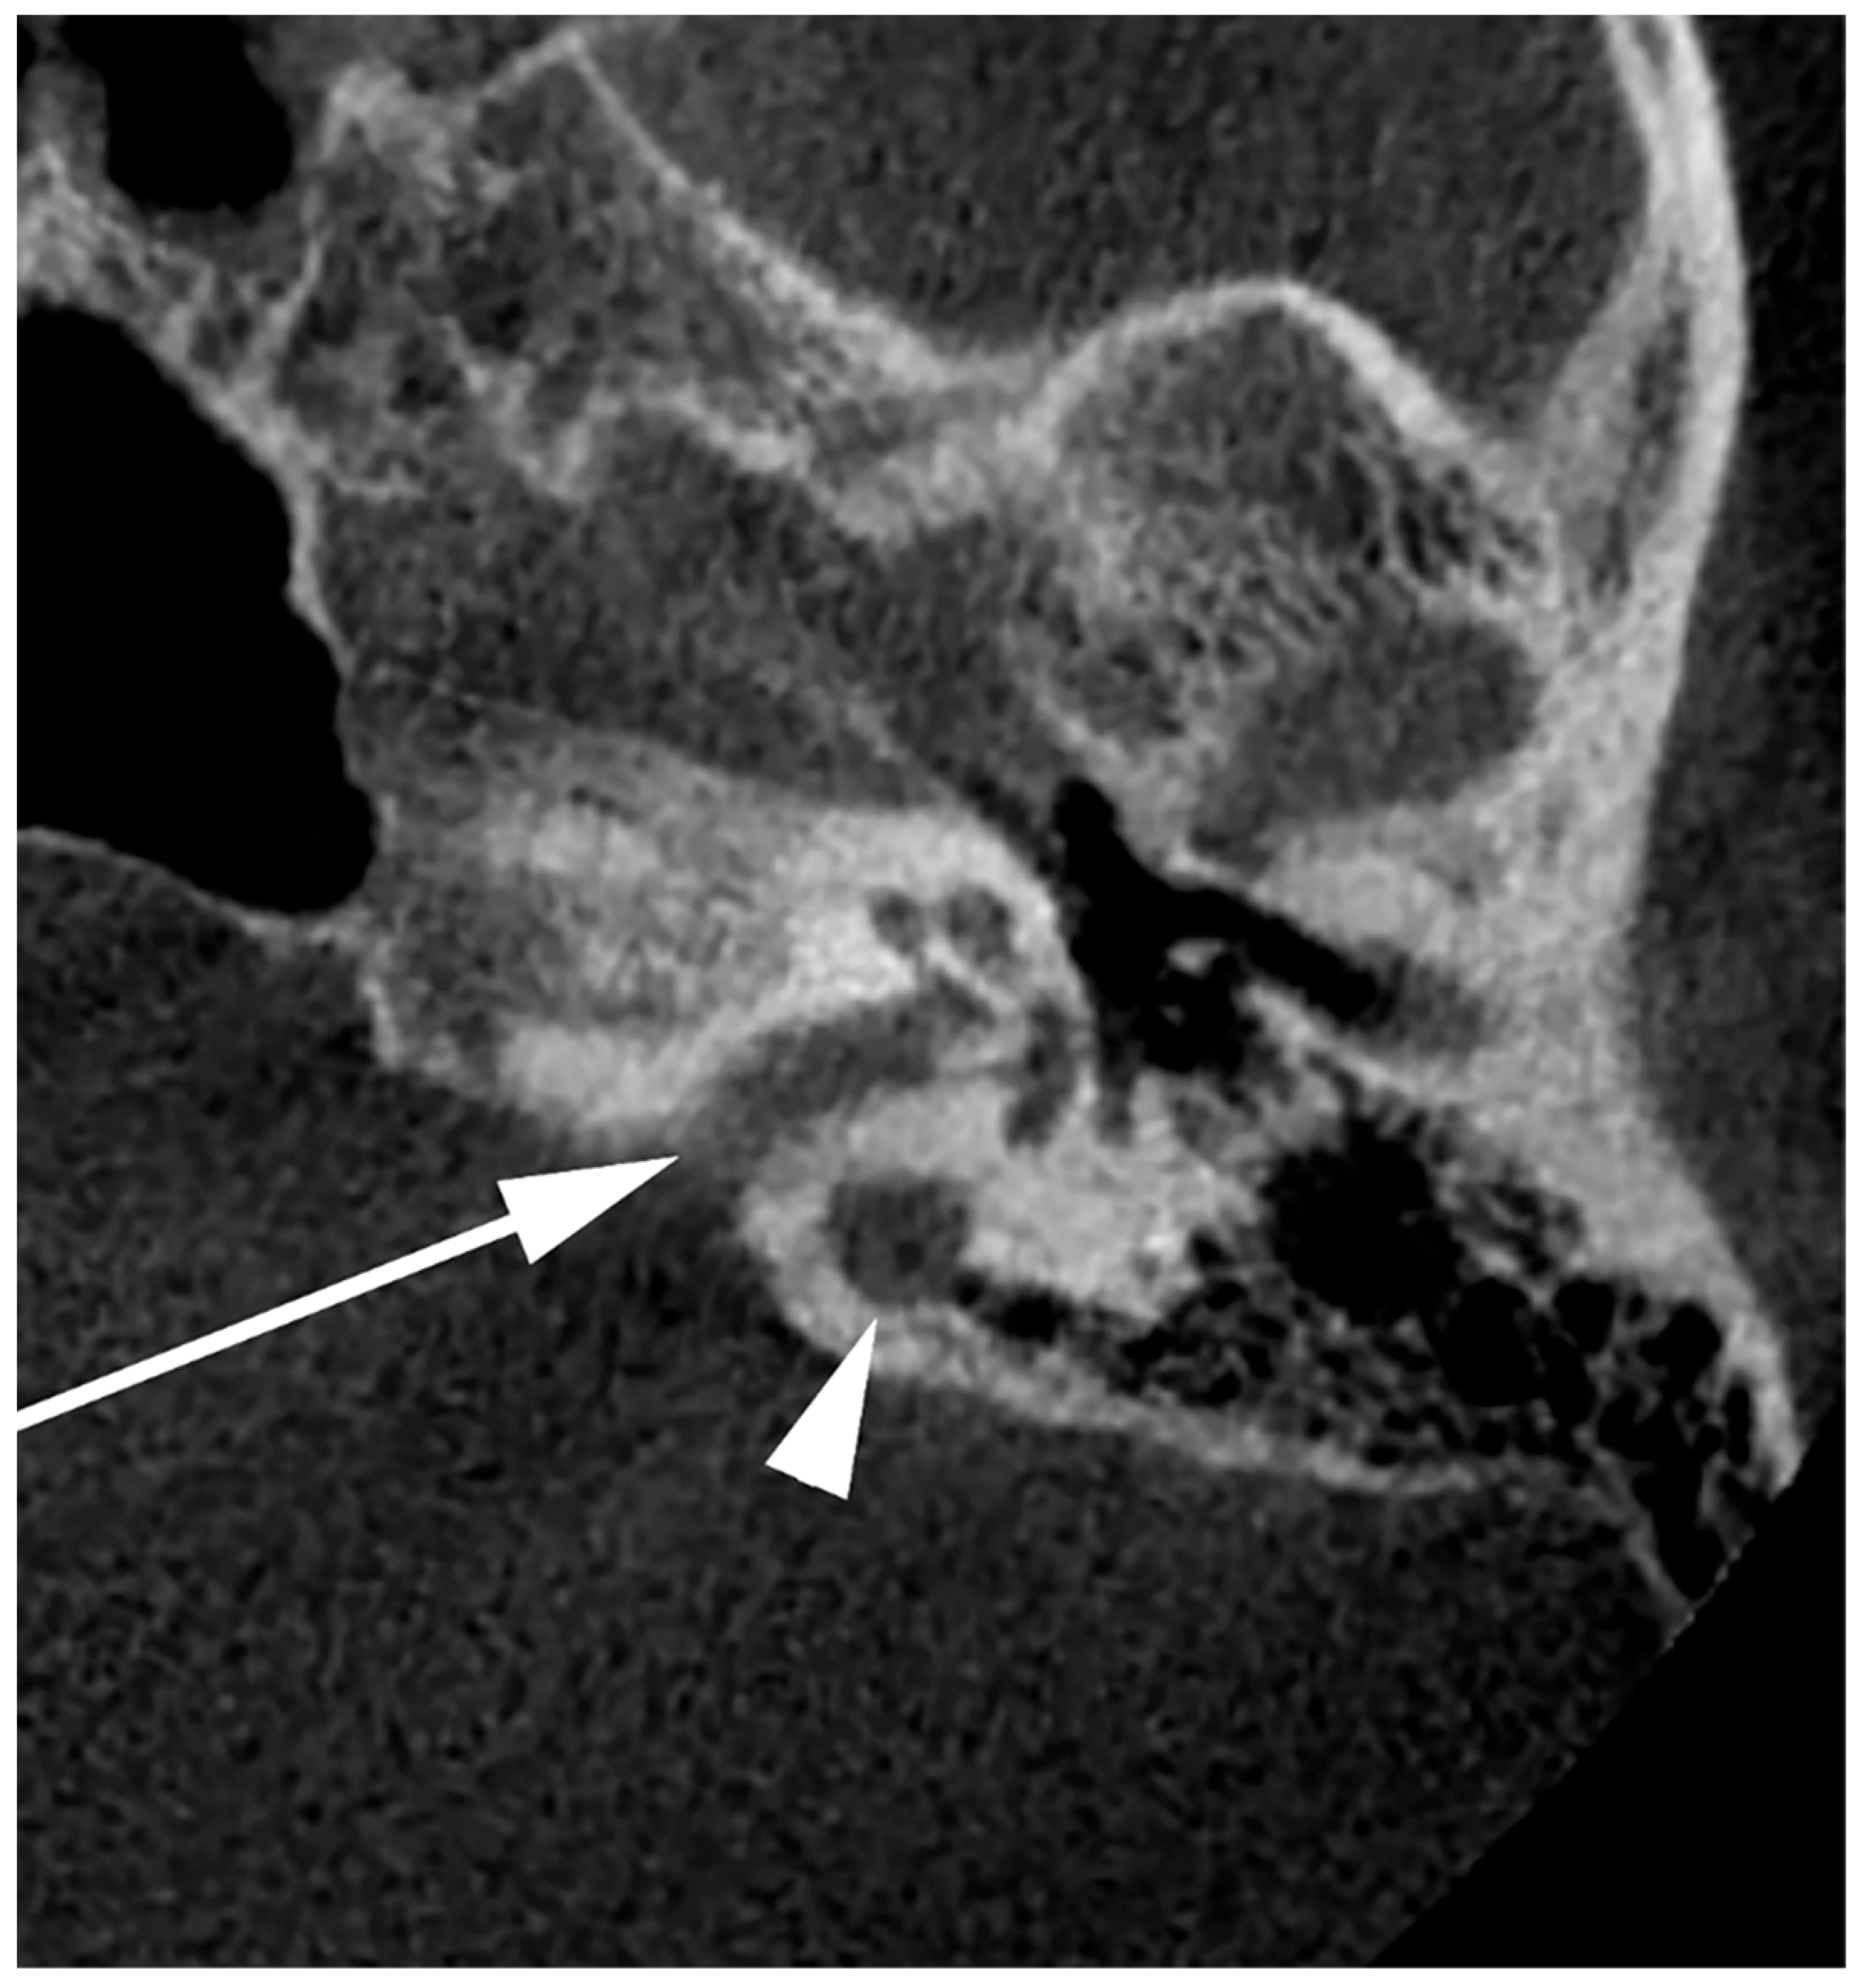

5. Dehiscent Jugular Bulb